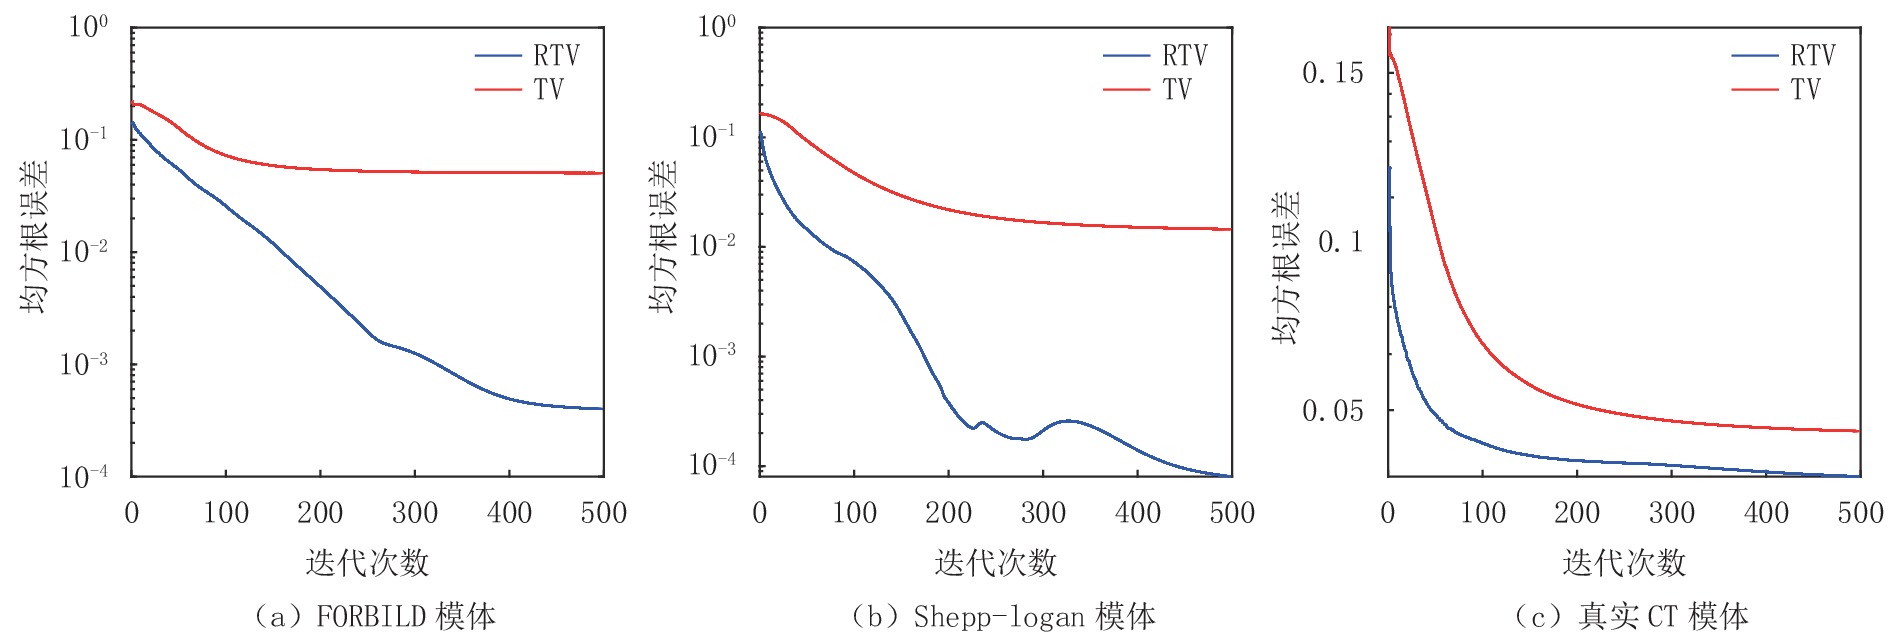

3.2 算法稀疏重建能力的评估与正则项各参数的选取

为了评估RTV算法的稀疏重建能力,本节实验分别使用RTV算法和TV算法对FORBILD、Shepp-Logan和真实CT图像模体在20,30,40,50个投影角度下进行模拟实验。这些模体的大小都是128

$ \times $ 128。在实验分析中,使用均方根误差(RMSE)和结构相似性(structural similarity,SSIM)作为图像重建质量的度量。在文献[2]对ASD-POCS算法的阐述中,数据容差

$ \in $ 只强调与噪声强度有关,而本节实验投影数据不含噪声,所以将ε设为 0。对于RTV最小化迭代次数,设定为4,经过大量实验后发现4次迭代已经足够得到相对精确的结果,如果RTV最小化迭代次数偏大的话,重建结果会出现模糊,丢失细节等情况。对于算法的停止条件(stopping criteria),可以设为当达到某个特定条件时结束,如

${{\big\| {{{\boldsymbol{f}}^{(n)}} - {{\boldsymbol{f}}^{(n - 1)}}} \big\|} \mathord{\left/ {\vphantom {{\big\| {{f^{(n)}} - {f^{(n - 1)}}} \big\|} {\big\| {{f^{(n - 1)}}} \big\|}}} \right. } {\big\| {{{\boldsymbol{f}}^{(n - 1)}}} \big\|}} \leq {10^{ - 4}}$ 时结束迭代。但是为了更直观地分析算法迭代过程中RMSE曲线的收敛特性,在本节实验里,将算法的停止条件设为迭代500次后,结束循环。对于RTV正则项的权重参数λ,它影响着算法在保留更多原始投影数据内容和去除噪声之间的平衡。如果λ过大,会增加正则项的权重,这样的话,会导致重建算法在去除更多噪声信息的同时,也会平滑模糊掉重建图像的更多细节;相反,如果λ较小的话,数据保真项的权重会增加,重建图像可能将会过拟合给定的投影数据,相应的数据中的噪声也会被更多地保留。所以,合适的选择是在去噪和保留重建图像细节之间找到一个使两者实现平衡的数值,通过大量实验所得到的经验来看,选择λ=0.45,可以在很好地抑制伪影的同时有效地保护图像结构和细节。

图6中的(a)图显示了FORBILD模体在20个投影角度下使用RTV和TV最小化重建算法的RMSE趋势曲线的比较,显然,RTV最小化重建算法经过500次迭代达到收敛点后拥有更高的重建精度,其最终的收敛精度是30×10-5。而TV算法最终的收敛精度只有5130×10-5。

表 1 RTV算法和TV算法重建FORBILD模体的RMSE和SSIM比较Table 1. RMSE and SSIM comparison of RTV and TV algorithms for FORBILD phantom reconstruction项目 算法 投影个数 20 30 40 50 RMSE RTV 30.0×10-5 9.96×10-5 7.11×10-5 5.60×10-5 TV 5130×10-5 2530×10-5 620×10-5 590×10-5 SSIM RTV 0.9587 0.9792 0.9972 0.9992 TV 0.9293 0.9583 0.9943 0.9986 图7显示了两种算法关于FORBILD模体的重建结果。在20个投影角度下,TV算法重建结果有明显的伪影和噪点,并且有多处图像细节也被平滑掉。从20个到50个投影角度,其重建图像的精度虽然不断升高,不过一直到50个投影角度时,其重建图像与原图相比还是有些明显的伪影。而同样在20个投影角度的情况下,RTV最小化算法重建结果用肉眼几乎看不出与原图的区别。随着投影角度的增加,其重建结果与原图相比还是一致的。显然RTV算法的重建效果更好一点。

图8显示了两种算法关于Shepp-Logan模体的重建结果,通过对比,可见在20个投影角度下,RTV最小化重建算法的重建结果与原图相比用肉眼几乎看不出与原图的区别。而TV最小化算法在20个投影角度下的重建结果对于图像结构的保护还是有所欠缺,模糊了较多的细节。但随着投影角度的增加,其重建精度也越来越高,两种算法的重建结果与原图相比都几乎一样。

图6中的(b)图显示了Shepp-Logan模体在20个投影角度下使用RTV和TV最小化重建算法的RMSE趋势曲线的比较,显然,RTV最小化重建算法经过500次迭代达到收敛点后拥有更高的重建精度,其最终的收敛精度是8.010×10-5。而TV算法最终的收敛精度只有1610×10-5。

表 2 RTV算法和TV算法重建Shepp-Logan模体的RMSE和SSIM比较Table 2. RMSE and SSIM comparison of the RTV and TV algorithms for Shepp-Logan phantom reconstruction项目 算法 投影个数 20 30 40 50 RMSE RTV 8.010×10-5 4.791×10-5 3.349×10-5 2.586×10-5 TV 1610×10-5 530×10-5 160×10-5 80×10-5 SSIM RTV 0.9866 0.9948 0.9978 0.9995 TV 0.9812 0.9923 0.9956 0.9991 图9显示了两种算法关于真实CT图像模体的重建图像。在20、30个投影角度下,TV算法明显平滑掉了更多地图像细节,尤其在30个角度下的实验结果里,相比与RTV最小化算法,其重建结果的下面明显有更多伪影。显然,使用RTV最小化算法可以更好地保护图像结构。

图6中的图(c)显示了真实CT模体图像在20个投影角度下使用RTV和TV最小化重建算法的RMSE趋势曲线的比较,显然,RTV最小化重建算法经过500次迭代达到收敛点后拥有更高的重建精度,其最终的收敛精度是0.0403。而TV算法最终的收敛精度只有0.0467。

图11显示了FORBILD、Shepp-Logan和真实CT模体图像在50个投影角度,并于投影数据中加入方差为0.05的高斯白噪声条件下分别使用RTV和TV最小化重建算法进行重建的RMSE趋势曲线的比较,从表4~表6中的数据可见这两种算法在3个模体上的重建精度分别为0.005和0.01842、0.0055和0.0148、0.0233和0.0286,从定量分析来看显然RTV最小化算法抑制噪声,保护图像结构的效果更好一点。